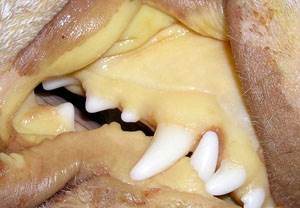

У некоторых собак и кошек развивается желтуха (желтое окрашивание белков глаз, десен, внутренней поверхности ушной раковины, открытых участков кожи).